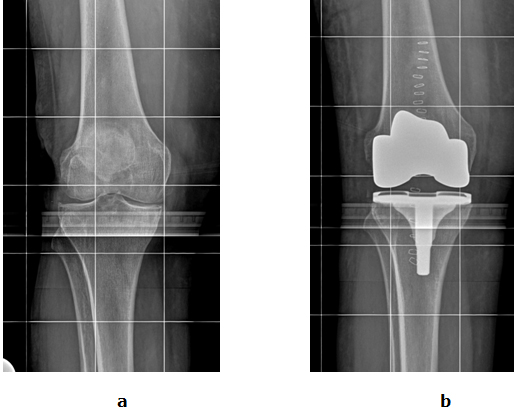

Ist das gesamte Kniegelenk von der Arthrose betroffen, wird der sogenannte Oberflächenersatz verwendet. Der körpereigene Bandapparat bleibt erhalten und steuert weiterhin die Beweglichkeit des Gelenks. Bei beiden Formen des Kniegelenkersatzes darf schon am Folgetag an Unterarmgestützen voll belastet werden.

Abb. 2: a Arthrose des gesamten Kniegelenkes. b Die Oberfläche vom Inneren und Äußeren Gelenkanteil sind durch ein Kunstgelenk ersetzt (Oberflächenersatz).